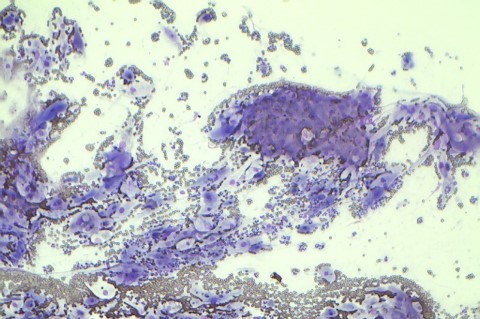

Zytologie

Aus Feinnadelpunktionen oder Körperflüssigkeiten gewonnene Zellen können unter dem Video-Mikroskop anhand ihrer Zellkriterien untersucht werden. So kann oft schon ohne größere Eingriffe entschieden werden ob eine Umfangsvermehrung oder ein Körperhöhlenerguss gut- oder bösartigen Ursprungs ist. Die Punktion kann im Gegensatz zu Biopsie in den meisten Fällen ohne Allgemeinnarkose durchgeführt werden.